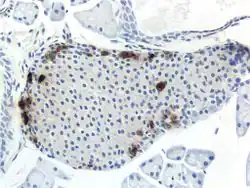

Pancreatic Polypeptide From a Mouse Cell

Through different microscopy techniques, the structural related details of PP cells have been able to be better understood. This is inclusive of how big they are, what their cellular membranes look like, the proteins associated with them, and even their size. PP cells are elongated cells. Another one of these details can be noted in insulins secretory granules, or container like buds, that store insulin within a cell. In PP cells, the size of the insulin granules are smaller and spherical and similar to those in alpha cells. This is noted in human PP cells, but different animals have been shown to have different sized granules compared to humans, like rodents. In cats and dogs, PP cells have large granules.[6] In rats, PP cells have few granules, similar to humans. In dogs, some PP cells are located in the walls of the antrum of the stomach.[3]